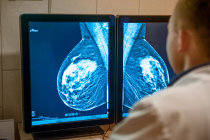

O diagnóstico23 de mastite1 ou de abscesso24 mamário pode ser feito com base apenas na história clínica e no exame físico. Se o médico não tiver certeza se a massa que ele detectou na mama8 é um abscesso24 ou um tumor25, uma ultrassonografia26 de mama8 pode ser realizada, porque ela fornecerá mais clareza sobre o caso.

Em casos de mastite1 infecciosa, podem ser necessárias culturas do leite materno ou do material aspirado do abscesso24, para determinar que tipo de organismo está causando a infecção4 e para decidir o tipo específico de antibiótico que será utilizado na cura da doença. Mamografias ou biópsias27 mamárias são normalmente realizadas em mulheres que não respondem ao tratamento ou em mulheres que não amamentam. Esse tipo de teste é solicitado para excluir a possibilidade de um câncer28 de mama8 que cause sintomas17 semelhantes aos da mastite1.